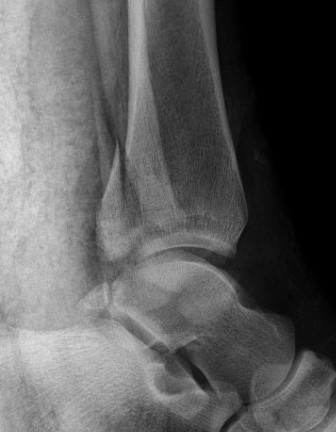

1. Large fragment / ankle joint subluxation

2. Articular incongruency / articular step

3. Syndesmotic involvement

Dislocated ankle joint with large posterior malleolus

Articular incongruency

Posterior malleolus and syndesmotic injury